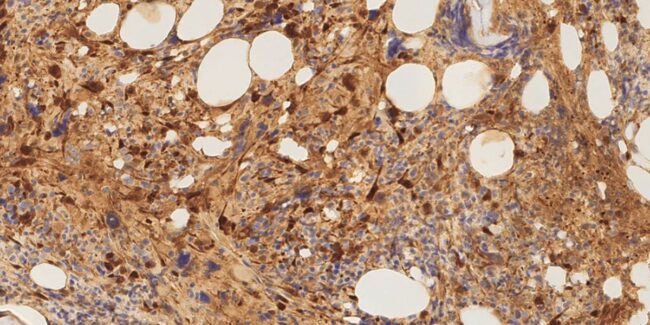

El Centro de Medicina Comparada (ICIVET Litoral, CONICET-UNL) ha recertificado la conformidad con las Buenas Prácticas de Laboratorio (OCDE) ante el Organismo Argentino de Acreditación para la realización de estudios no clínicos y estudios toxicológicos, junto con otras normas nacionales e internacionales. (Foto: CONICET). El Centro de Medicina Comparada (CMC) forma parte del Instituto de Ciencias Veterinarias del…